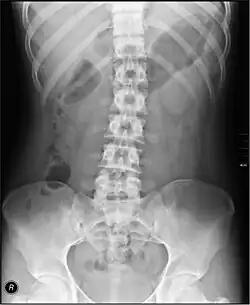

Diseases affecting the large intestine may cause blood to be passed with stool, may cause constipation, or may result in abdominal pain or a fever. Tests that specifically examine the function of the large intestine include barium swallows, abdominal x-rays, and colonoscopy.[5]: 913–915